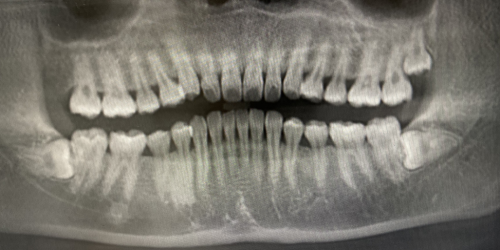

我想了解一下我有四颗智齿对牙齿矫正有很大影响吗但是我现在还不想

这是我x光片,左边上下两颗智齿长成年了没,还会继续长吗,没问题就留着